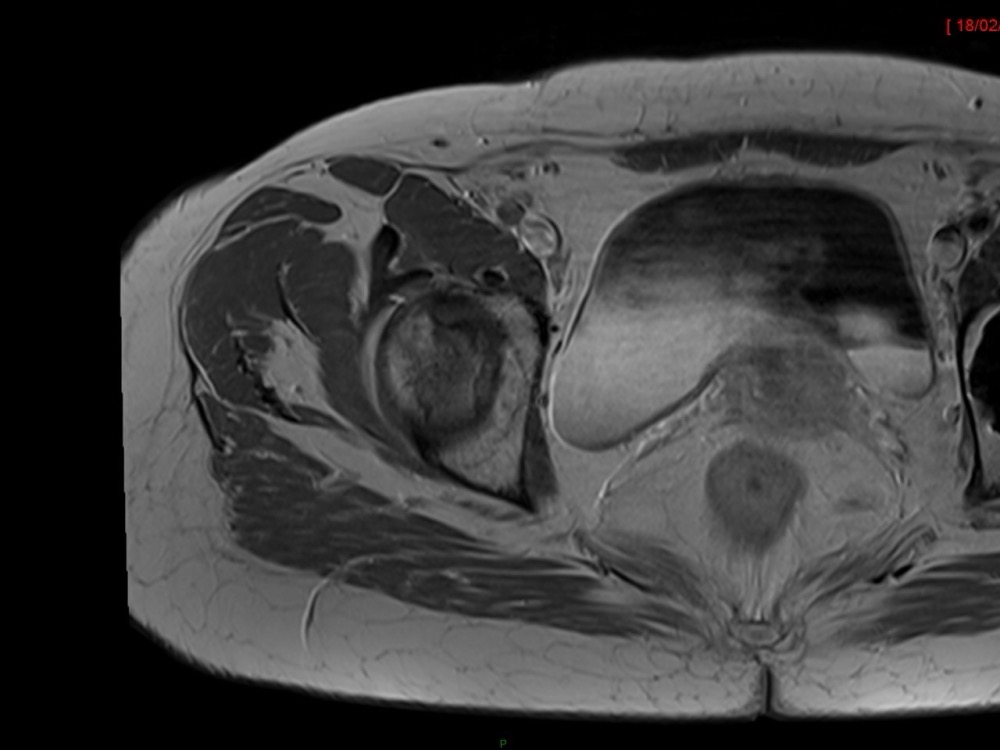

Aboudaram / Burns 11/01/2023